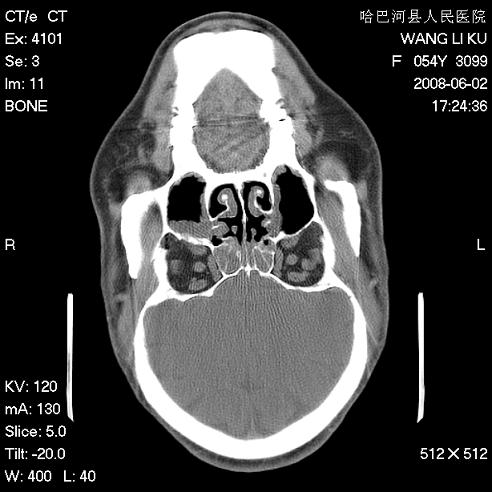

标题: CT13803:反复性鼻塞、流涕一年余 [打印本页]

标题: CT13803:反复性鼻塞、流涕一年余

副鼻窦炎,右上额窦积脓。左眼肌锥内见致密影,视神經受压

1.全组副鼻窦炎2.双侧上颌窦积液

全组副鼻窦炎 肌锥内高密度灶。建议进一步检察检查

1、全组副鼻窦炎。

2、左眼眶肌锥内病变,小血管瘤?建议增强。

1)全副鼻窦炎(左侧上颌窦黏膜下囊肿或息肉)。2)左眼眶肌锥内不规则小结节状软组织密度影;考虑为小血管瘤可能。建议行ct增强扫描检查。

全组副鼻窦炎,左侧肌锥内不规则形软组织肿块影,与眼外肌密度相当,左侧视神经受压,肿块与视神经及眼外肌分界清晰,眼外肌无增粗,眶壁无破坏,球后脂肪间隙不模糊,考虑良性改变,小血管瘤或神经源性肿瘤可能,建议增强扫描。

谢谢,增强扫描做了,眶内病灶与海绵窦同步明显强化,血管瘤